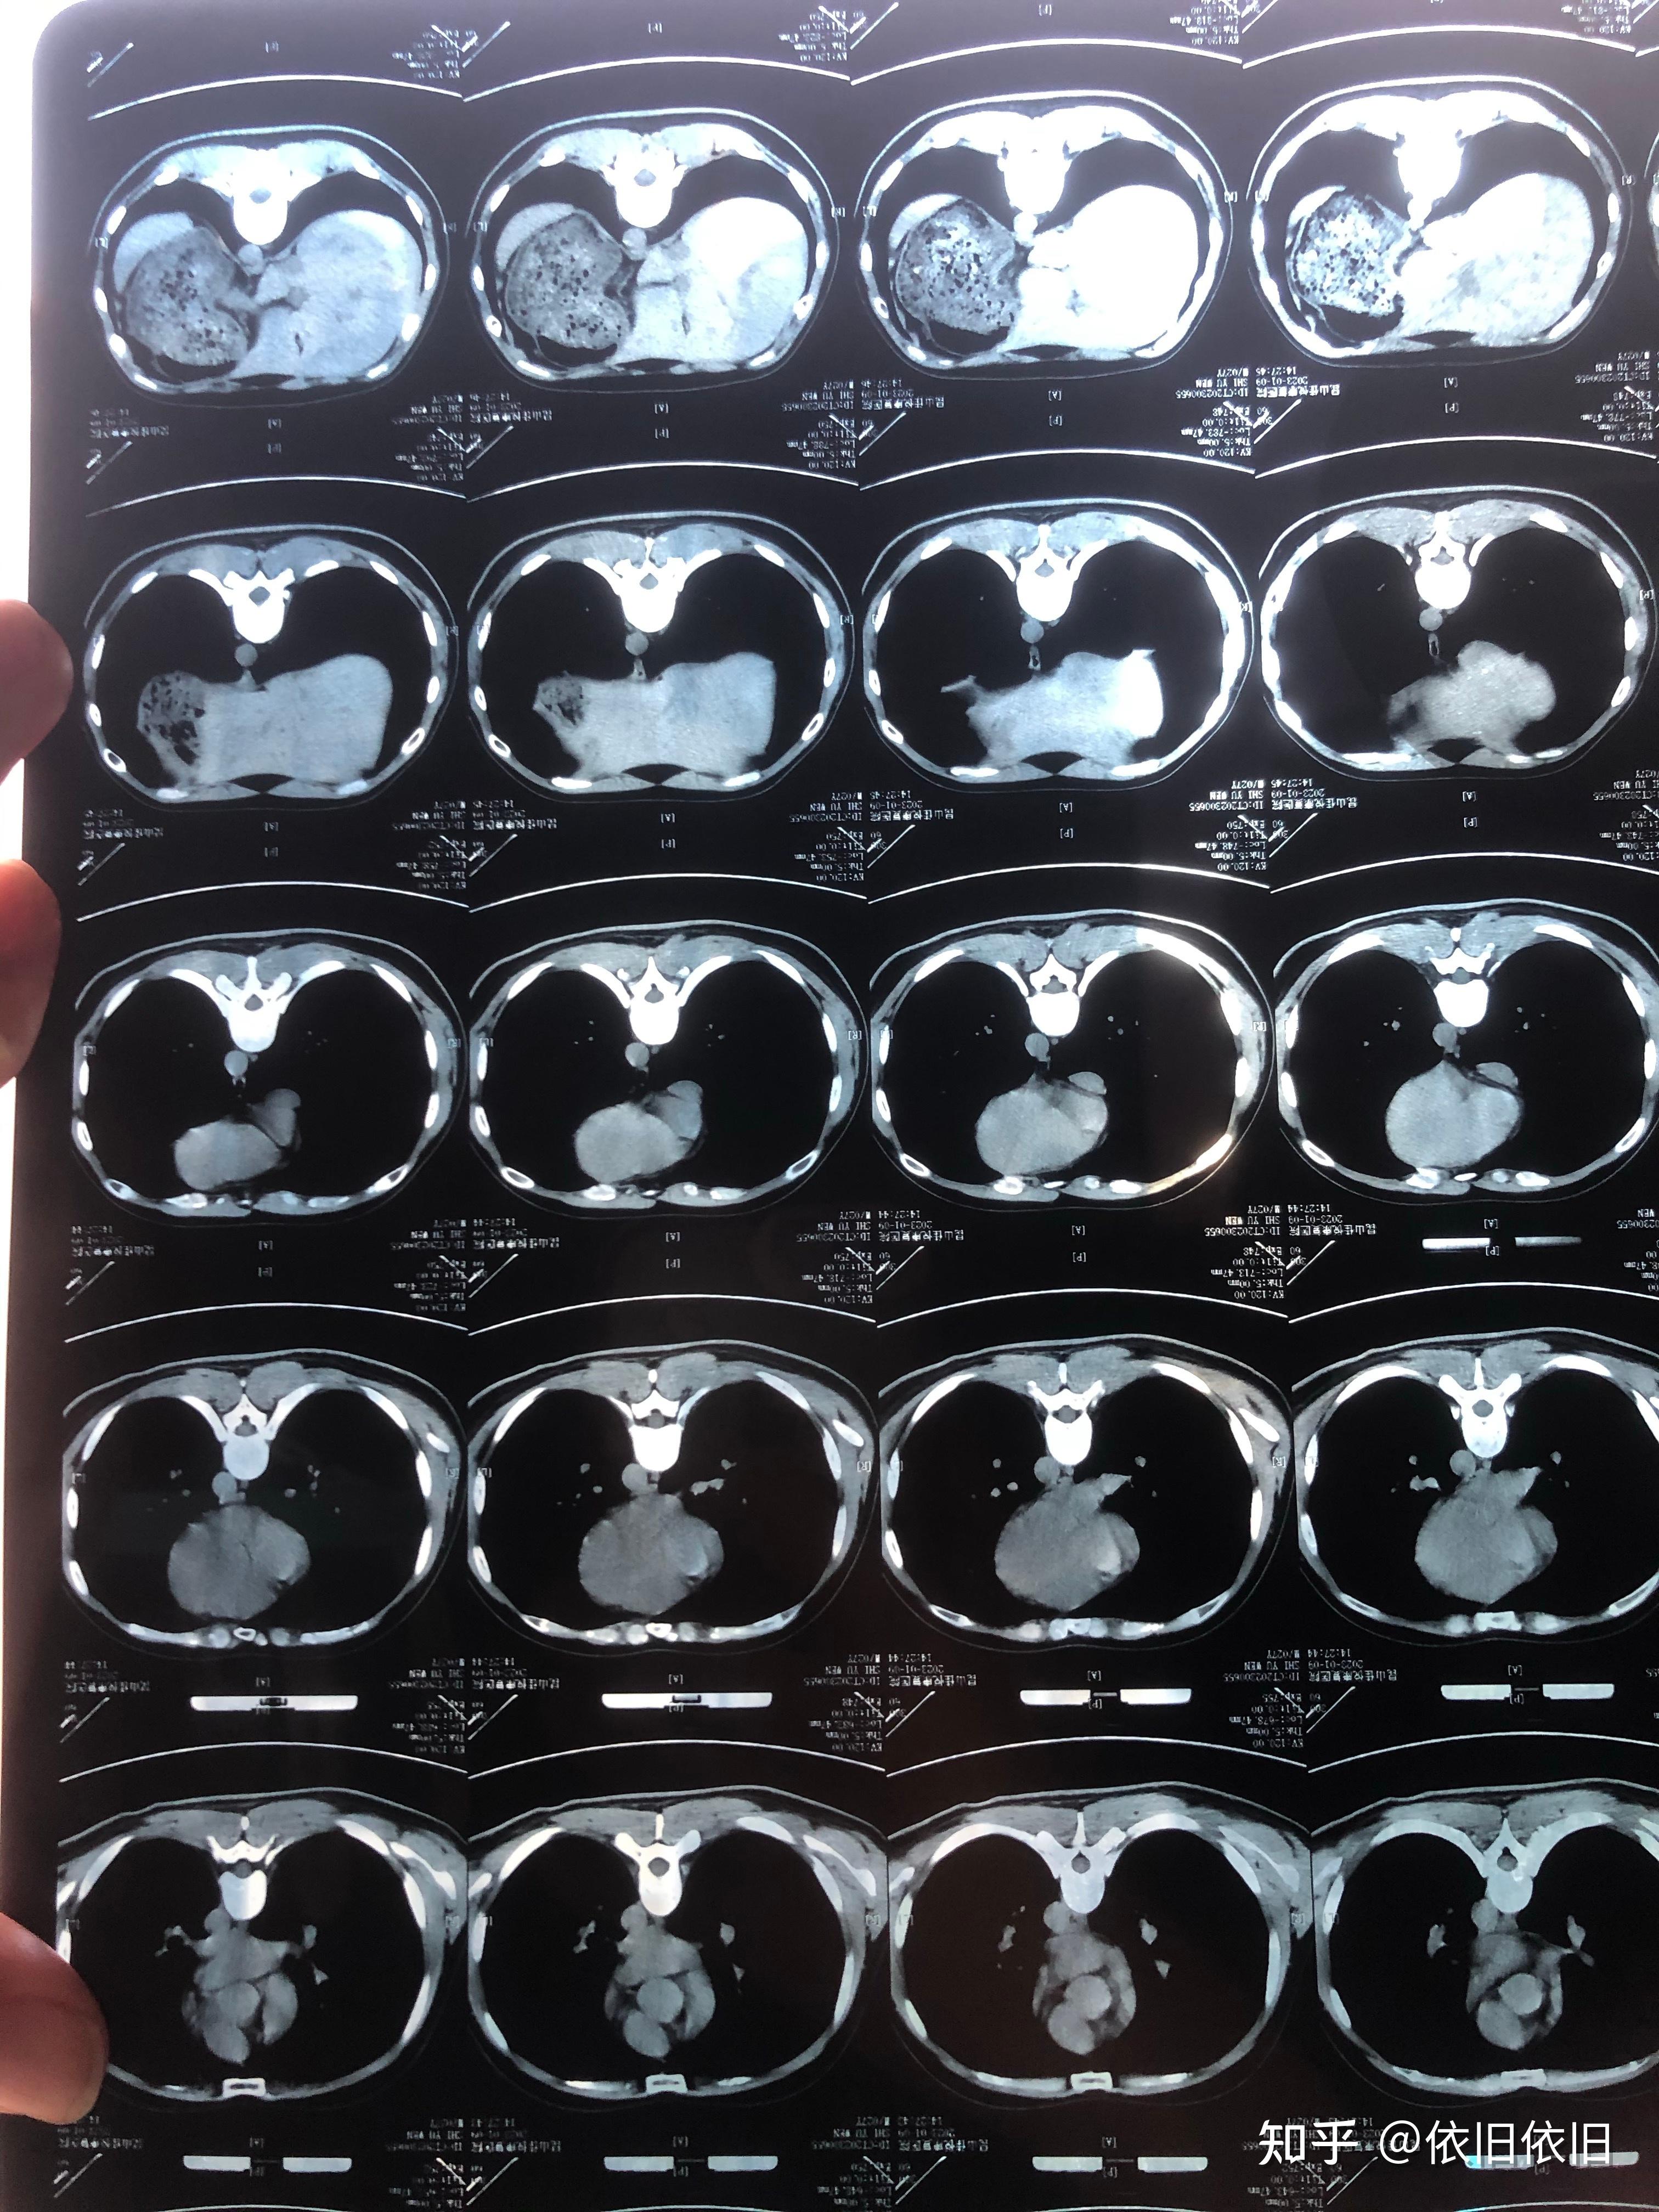

男性59岁,咳嗽,咳痰10余年,加重7天,胸部ct报告支扩并肺炎,考虑什么病